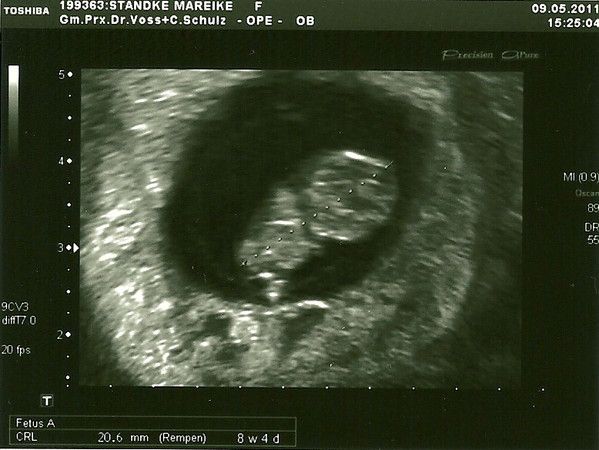

(Wäre schön wenn alle ihren Namen dazu schreiben würden)

Mein kleiner Siegelring

03.05.2011

Man sieht wirklich noch gar nichts! Das dicke Ende, also quasi das Siegel am Ring, ist mein Wurm. Noch nicht mal ein Gummibärchen, aber das Herz hat schon geschlagen. In 2 Wochen gibt´s das nächste Bild. FREU!!!